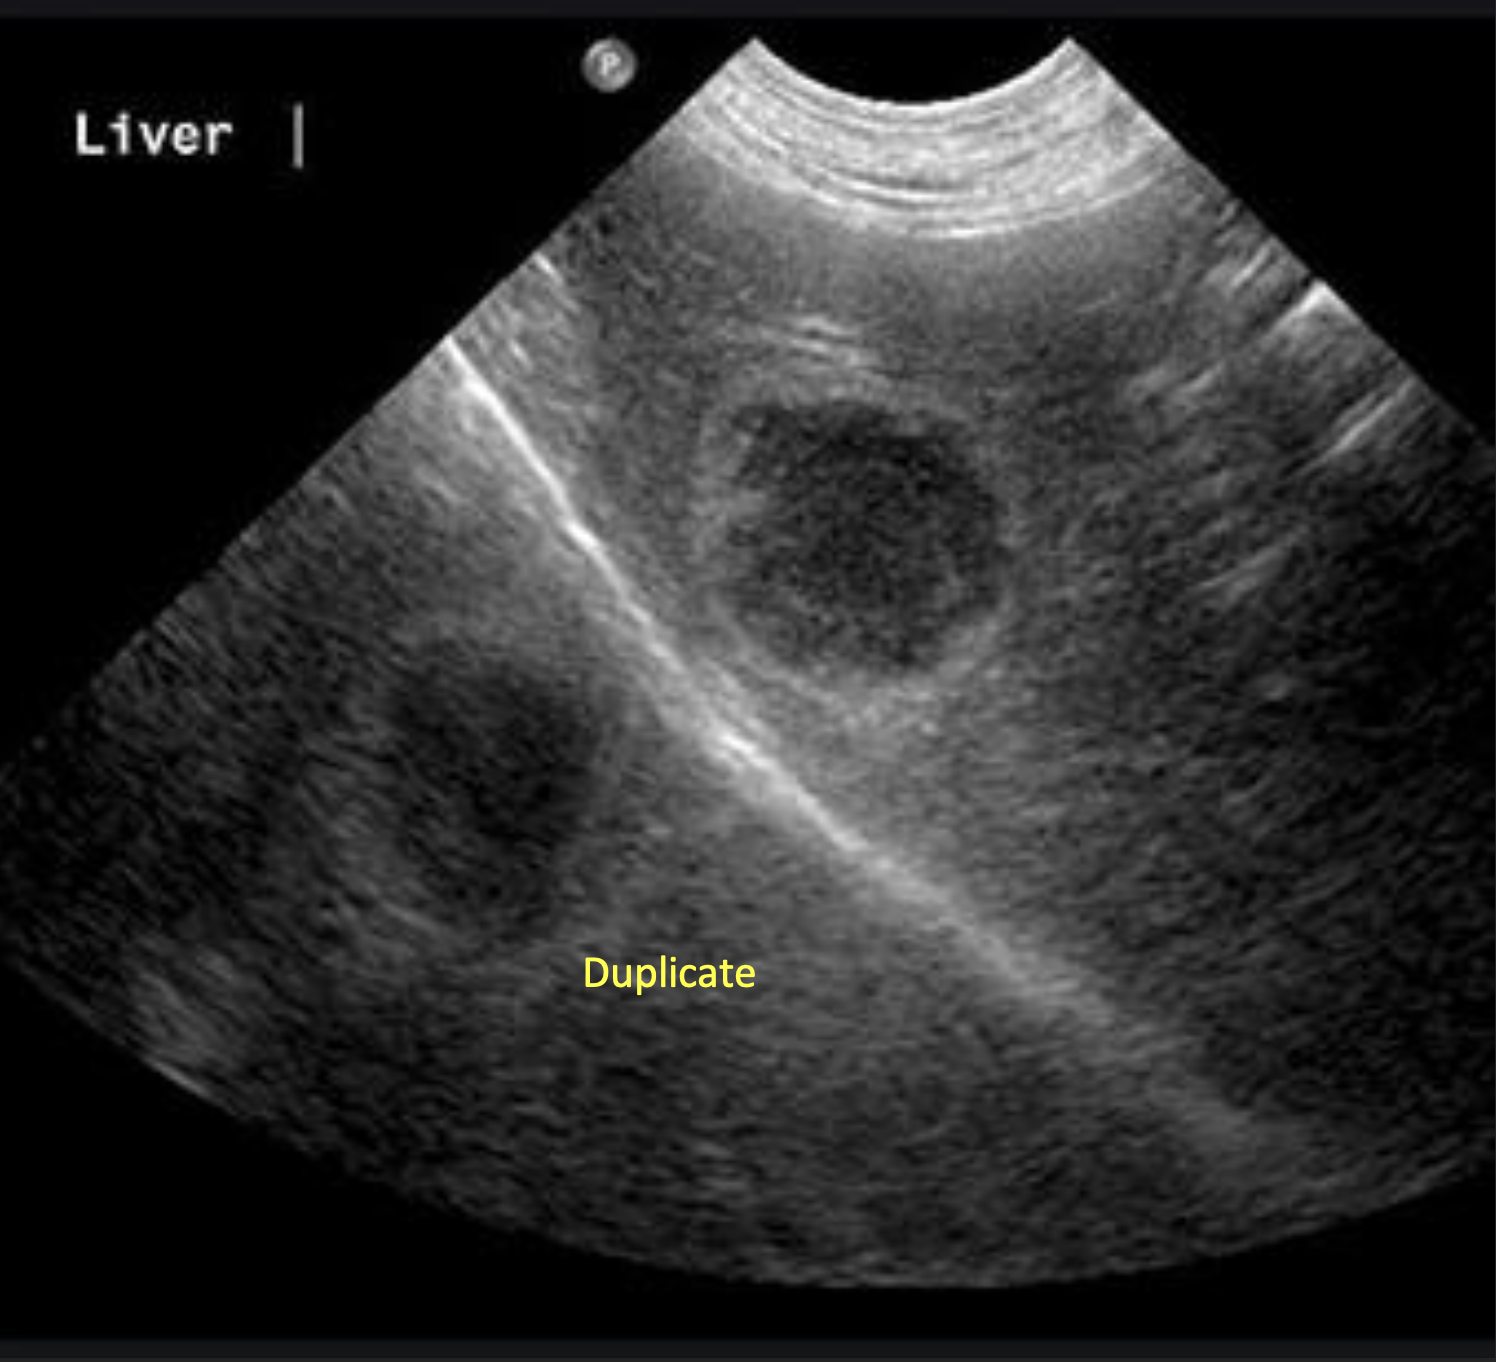

What ultrasound artifact can be seen from imaging a 3D structure with anechoic fluid?

Slice Thickness Artifact

Where does Slice Thickness Artifact most commonly occur?

Gall Bladder and Bladder

can see artificial sludge